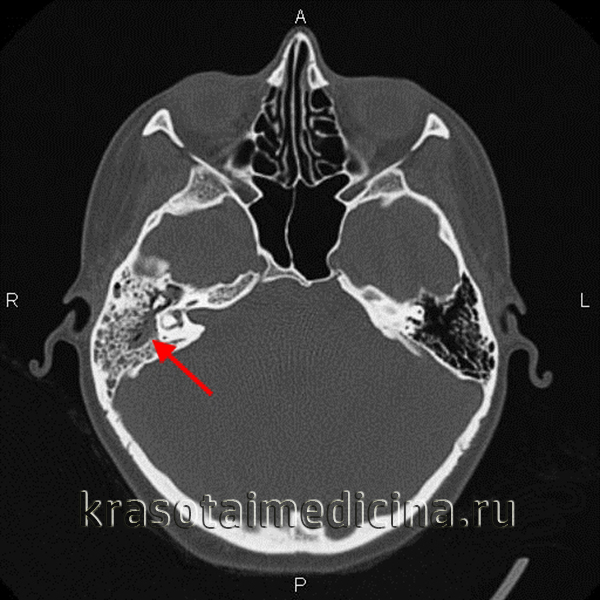

КТ височных костей. Тотальное снижение пневматизации ячеек сосцевидного отростка с обеих сторон. (фото Вишняков В.Н.)

• К рентгенологическим признакам, выявляемым на снимках в проекции Шюллера и на КТ височной кости, относятся снижение рентгенопрозрачности из-за уменьшения содержания воздуха в дыхательной системе, матовое затемнение сосцевидных ячеек, нечеткое изображение тонкой структуры кости в результате декальцификации и разжижения костных септ между сосцевидными ячейками, деструкция кости с очагами разжижения и эрозии соседних структур.

- Рентгенография височной кости. В экссудативной стадии мастоидита обнаруживает завуалированные в результате воспаления ячейки и нечетко различимые перегородки между ними. Рентгенологическая картина пролиферативно-альтеративной стадии мастоидита характеризуется отсутствием ячеистой структуры сосцевидного отростка, вместо которой определяется одна или несколько больших полостей. Лучшая визуализация достигается при проведении КТ черепа в области височной кости.

• очаг расплавления воздухоносных ячеек сосцевидного отростка на КТ височной кости;